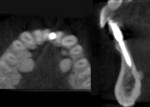

During the clinical examination, a narrow space of 3.5 mm was noted between the mandibular left lateral incisor (ie, tooth No. 23) and the right central incisor (ie, tooth No. 25) cervically. A CBCT scan was acquired to further evaluate the dimensions of the edentulous site. Using cross-sectional, coronal, and panoramic views of the site, it was determined that there was 4.5 mm between the buccal and lingual osseous limits of the space (Figure 1 and Figure 2). The adjacent incisors exhibited normal mobility, probing depths that were within normal limits, and no restorative issues. Following clinical examination and evaluation of the CBCT scan, a treatment plan was recommended that involved placing a one-piece, narrow-diameter implant that the space would accommodate, immediately placing a provisional restoration, and then fabricating and delivering a final restoration after a 4-month healing period to allow for osseointegration and soft-tissue maturation around the implant and provisional restoration. As an alternative treatment option, the patient was informed that a conventional 3-unit fixed prosthesis utilizing the adjacent natural teeth for support was also a possibility.